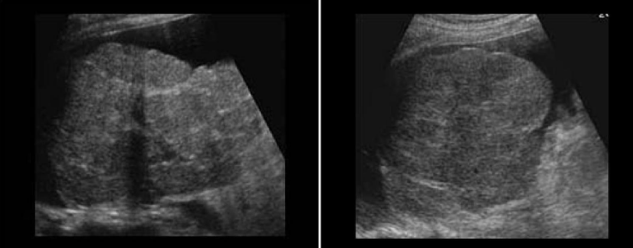

Identify this image.

Polycystic liver disease (PCLD)